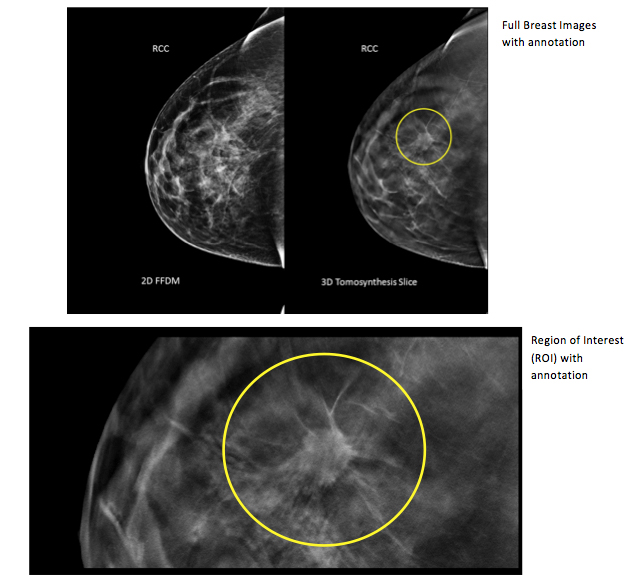

Standard mammograms typically take one image of each breast from two positions, while 3-D scans take several images of different layers of each breast. That allows for the detection of tumors that might be hidden under breast tissue and not noticeable on regular images, said Jim Culley, a spokesman for Hologic, which makes mammogram machines, including the combo ones used in the study that take both kinds.